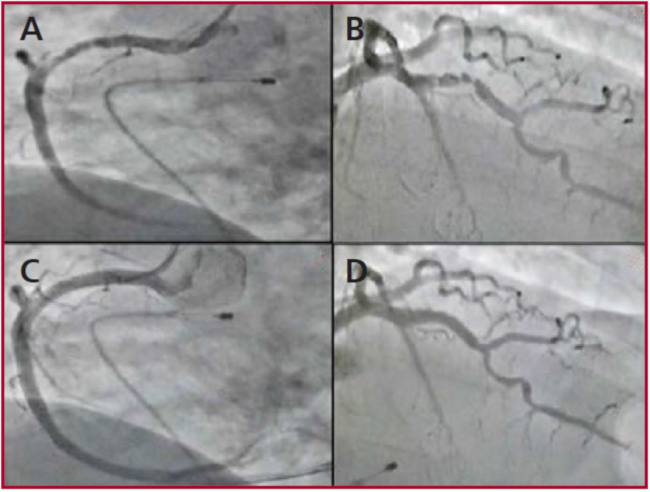

Presentamos el caso de un hombre de 68 años con antecedentes de tabaquismo y diabetes mellitus tipo 2, sin otro antecedente personal o familiar de enfermedades, quien fue atendido en el servicio de urgencias por un episodio de una hora con dolor torácico, disnea y diaforesis. Al examinarlo, presentaba frecuencia cardíaca de 40 latidos por minuto (lpm) y presión arterial media de 70 mmHg. Se encontraba nervioso; la auscultación reveló bradicardia con ruidos respiratorios normales, el resto del examen fue normal. El electrocardiograma (ECG) inicial mostró una lesión subepicárdica en la pared anterior e inferior con compromiso del ventrículo derecho (VD), y un bloqueo atrioventricular (AV) de 3.o grado (Figura 1). El paciente recibió tratamiento con aspirina 300 mg, clopidogrel 300 mg, enoxaparina 30 mg y un único bolo de tenecteplasa ajustado por peso dentro de los primeros 15 minutos del diagnóstico de infarto de miocardio. Sin embargo, el paciente desarrolló shock cardiogénico y el ECG no mostró ningún criterio de reperfusión 60 minutos después de la trombólisis. En ese momento, los indicadores de riesgo del IMEST fueron GRACE 181 puntos (40% de probabilidad de muerte desde el ingreso hasta los 6 meses) y TIMI 9 puntos (35,9% de riesgo de mortalidad por cualquier causa a los 30 días). El paciente fue entonces trasladado a la unidad de cateterismo cardíaco para someterlo a una angioplastía de rescate con soporte de norepinefrina y dobutamina. En primer lugar, se colocó un electrodo de marcapasos en el ventrículo derecho a través de la vena femoral y se programó en modo VVI con una frecuencia de 70 lpm; la angiografía coronaria mostró trombo intraluminal y un 70% de estenosis en el segmento proximal de la arteria coronaria derecha (CD) con flujo TIMI 2. Simultáneamente, la arteria descendente anterior (DA) izquierda mostró trombo intraluminal y estenosis del 80% en el segmento medio con flujo TIMI 2. Se implantó un stent liberador de everolimus (Xience-Alpine: 4,0 × 28 mm) en la CD y dos stents liberadores de everolimus (Xience-Alpine: 3,5 × 18 mm y 4,0 × 18 mm) se implantaron en la DA con superposición de stents. La última angiografía mostró las dos arterias con flujo TIMI grado 3 (Figura 2). Posteriormente, el ECG mostró un ritmo sinusal normal y marcadores de reperfusión con normalización del segmento ST de las inversiones del segmento ST y de la onda T en las derivaciones afectadas. El ecocardiograma reveló discinesia del VD con un cambio del área fraccional del 22% y fracción de eyección del ventrículo izquierdo del 46%. El soporte inotrópico y los vasopresores fueron suspendidos en menos de 48 horas. Tras la rehabilitación cardíaca en el hospital, el paciente finalmente fue dado de alta 8 días más tarde con seguimiento médico en los consultorios externos de cardiología. En la última consulta cardiológica, seis meses después del evento, el paciente manifiesta no tener síntomas cardiovasculares en sus actividades diarias ni tampoco durante los ejercicios aeróbicos, por lo que su afección tiene una clase funcional I según la New York Heart Association.